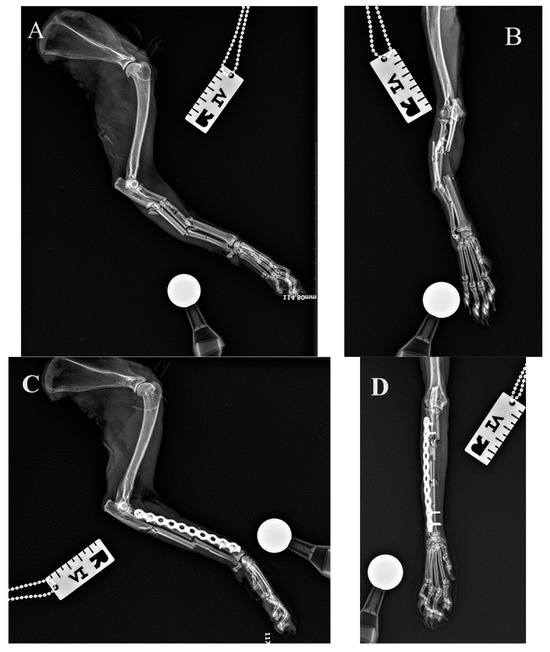

Figure 7. Initial lateral and cranio-caudal radiographs of the right forelimb of a female domestic longhaired cat with a comminuted antebrachial fracture (A,B). Radiographs after minimally invasive plate osteosynthesis (MIPO) of the radius (C,D). Correct alignment, adjacency, and apparatus were obtained.

The distal approach to the radius was first performed as described by Schmierer and Pozzi [16]. After creating the epiperiosteal tunnel with Metzenbaum scissors, the proximal approach was performed with additional elevation of the supinator muscle. After insertion of the plate, the first ∅ 2.4 mm cortical screw was tightened at the proximal end of the plate at the level of the radial neck. The bone fragment was then reduced under the plate using bone-holding forceps and the ∅ 2.4 mm locking screw was inserted into the second hole (Figure 6). The initially inserted cortical screw was then removed and the ∅ 2.4 mm locking screw was tightened in the same hole. After manual traction of the antebrachium and manipulation of the paw, the radial fracture was reduced and the distal end of the plate was screwed to the distal fragment of the radius in the same manner as described above (Figure 7).

All fractures were classified as complex diaphyseal fractures of radius and ulna: 22-C2 or 22-C3 in the AO VET fracture classification system [24]. In 40 cases, the axial and rotational alignment of the joints above and below the fracture was appropriate and attachment of the main fracture fragments to the comminution zone was adequate. Location, placement, and the size of the implants were all assessed as correct on postoperative radiographs. In two cases (two right limbs), the plate was fixed by mistake to the proximal radius and distal ulna (Figure 8 because the distal approach was made between the lateral digital extensor tendon and the carpi ulnaris tendon, rather than between the extensor carpi radialis tendon and the common digital extensor tendon. After revision surgery and correct fixation of the radius, the alignment, adjacency, and apparatus were all satisfactory.